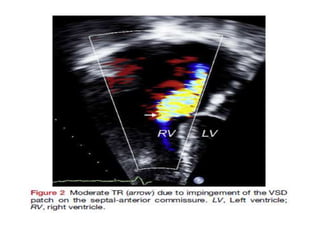

• TR is commonly encountered in patients with repaired TOF

and may be due to several factors.

• One mechanism involves disruption of the integrity of the

tricuspid septal-anterior commissure by the VSD patch. This

results in a TR jet originating at the junction between the VSD

patch and the septal attachment of the TV and extending

along the atrial septum.

• The mechanism of TR is determined by a combination of 2D, 3D,

and color Doppler flow imaging.

• Simultaneous depiction of 2D and color Doppler flow imaging

facilitates depiction of the TR jet relative to anatomic structures

seen on 2D images.